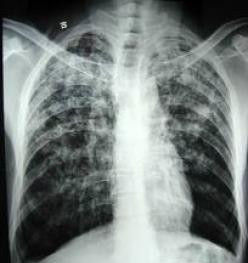

X線影像學對肺結核診斷有重要參考意義。(1)繼發性肺結核的胸部X線表現

繼發性肺結核胸部X線表現並無特異性,但常有如下特點:病變多發生在肺上葉尖後段、肺下葉背段,多肺段侵犯常見(少數病變也可局限),X線影像常呈多形態表現共存(同時呈現滲出、增殖、纖維和乾酪性病變),可伴有鈣化,易合併空洞,常伴有同側或對側支氣管播散灶,空洞或病灶內側可有引流支氣管征。呈球形病灶時(結核球)直徑多在3cm以內,周圍可有衛星灶。可伴有胸腔積液、胸膜增厚與粘連。病變經治療後吸收較慢(1個月內變化較小)。

3.胸部X線檢查是肺結核診斷的必要手段,繼發性肺結核胸部X線表現為多種形態混合存在,常可呈雲絮狀或斑點(斑片)結節狀,幹略性病變密度偏高而不均勻,常有透亮區或空洞形成。病期延長可同時出現纖維化或鈣化灶,結合上葉尖後段或下葉背段好發部位和X線特點可為診斷提供重要參考。